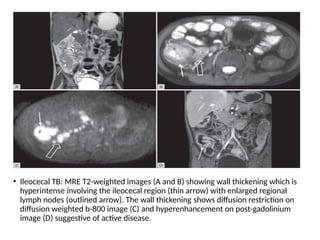

• Ileocecal TB: MRE T2-weighted images (A and B) showing wall thickening which is

hyperintense involving the ileocecal region (thin arrow) with enlarged regional

lymph nodes (outlined arrow). The wall thickening shows diffusion restriction on

diffusion weighted b-800 image (C) and hyperenhancement on post-gadolinium

image (D) suggestive of active disease.

• Ileocecal TB:MRE T2-weighted images (A and B) showing wall thickening which is hyperintense involving the ileocecal region (thin arrow) with enlarged regional lymph nodes (outlined arrow). The wall thickening shows diffusion restriction on diffusion weighted b-800 image (C) and hyperenhancement on post-gadolinium image (D) suggestive of active disease.